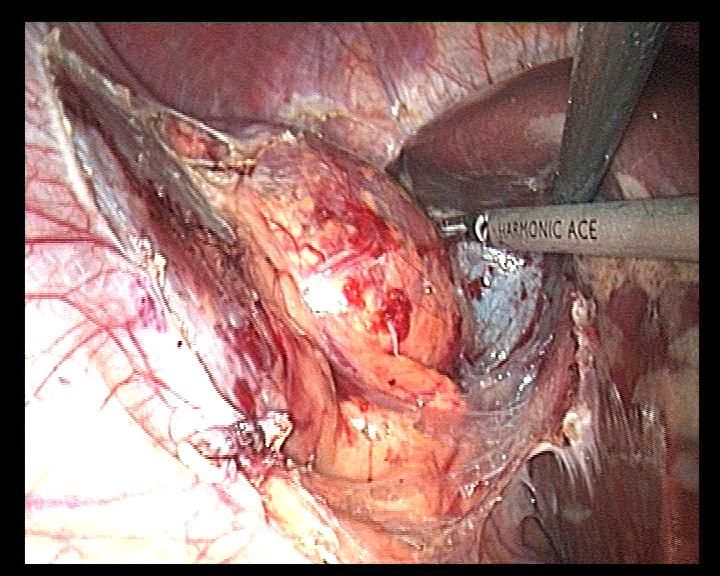

Source: Cancer Urology; Том 13, № 2 (2017); 121-123 ; Онкоурология; Том 13, № 2 (2017); 121-123 ; 1996-1812 ; 1726-9776 ; 10.17650/1726-9776-2017-13-2

Subject Terms: лапароскопическая адреналэктомия, adrenal myelolipoma, laparoscopic adrenalectomy, миелолипома надпочечника

Relation: https://oncourology.abvpress.ru/oncur/article/view/654/667; https://oncourology.abvpress.ru/oncur/article/downloadSuppFile/654/442; https://oncourology.abvpress.ru/oncur/article/downloadSuppFile/654/443; https://oncourology.abvpress.ru/oncur/article/downloadSuppFile/654/444; https://oncourology.abvpress.ru/oncur/article/downloadSuppFile/654/445; https://oncourology.abvpress.ru/oncur/article/downloadSuppFile/654/446; Dan D., Bahadursingh S., Harinaran S. et al. Extra-adrenal perirenal myelolipoma. A case report and review literature. G Chir 2012;33(3);62–5. DOI:10.11138/2012.33.5.62-5. PMID: 22525547.; Sanders R., Bissada N., Curry N., Gordon B. Clinical spectrum of adrenal myelolipoma: analysis of 8 tumors in 7 patients. J Urol 1995;153(6):1791–3. DOI:10.4103/0970-1591.152807. PMID: 7752318.; Han M., Burnett A.L., Fishman E.K., Marshall F.F. The natural history and treatment of adrenal myelolipoma. J Urol 1997;157(4):1213–6. PMID: 9120904.; Bhansali A., Dash R.J., Singh S.K. et al. Adrenal myelolipoma: profile of six patients with a brief review of literature. Int J Endocrinol Metab 2003;1:33–40.; Clark O.H., Duh Q.Y., Perriet N.D., Jahan T.M. Endocrine tumors. Atlas of Clinical Oncology. BC Decker, 2003.; Бондаренко В.О., Дэпюи Т.И., Бондаренко Е.В. и др. Миелолипома надпочечников. Эндокринная хирургия 2013;(4):25–38. [Bondarenko V.O., Depyui T.I., Bondarenko E.V. et al. Adrenal myelolipoma. Endokrinnaya khirurgiya = Endocrine Surgery 2013;(4):25–38. (In Russ.)]. DOI:10.14341/serg2013425-38.; Lin P., Yang F. Bilateral giant adrenal myelolipomas: a case report and literature review. Chin J Radiol 2008;33:261–4.; Wrightson W.R., Hahm T.X., Hutchinson J.R., Cheadle W. Bilateral giant adrenal myelolipomas: a case report. Am Surg 2002;68(6):588–9. DOI:10.1159/000078383. PMID: 12079144.; Fernandes G.C., Gupta R.K., Kandalkar B.M. Giant adrenal myelolipoma. Indian J Pathol Microbiol 2010;53(2):325–6. DOI:10.4103/0377-4929.64314. PMID: 20551546.; Chung H., Luo F., Wu T., Tsai Y. Adrenal myelolipoma with spontaneous hemorrhage. Urol Sci 2010;21(3):152–4.; Chakrabati I., Ghosh N., Das V. Giant adrenal myelolipoma with hemorrhage masquerading as retroperitoneal sarcoma. J Midlife Health 2012;3(1):42–4. DOI:10.4103/0976-7800.98818. PMID: 22923980.; Gerson G., Bêco M. Giant retroperitoneal myelolipoma: case report and literature review. J Bras Patol Med Lab 2015:48–51. DOI:10.5935/1676-2444.20150010.; Al Hatthi B., Riaz M.M., Al Khalaf A.H. et al. Adrenal myelolipoma a rare benign tumour managed laparoscopically: report of two cases. J Minim Access Surg 2009;5(4):118–20. DOI:10.4103/0972-9941.59312. PMID: 20407573.; https://oncourology.abvpress.ru/oncur/article/view/654